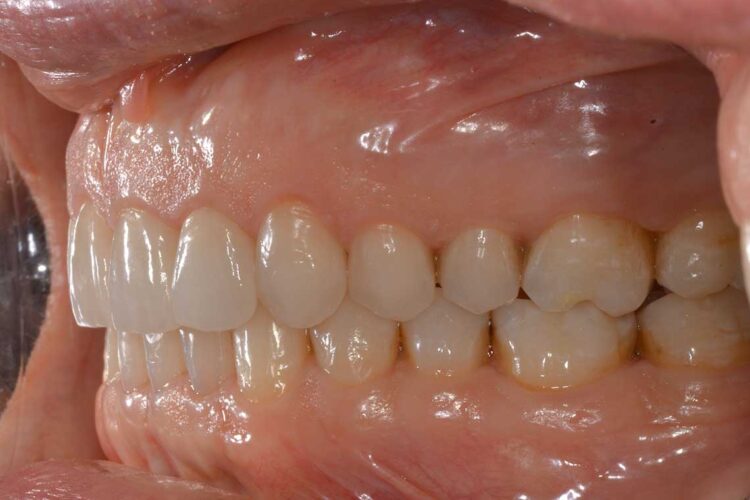

Ortodonzia allineatori – caso clinico 2